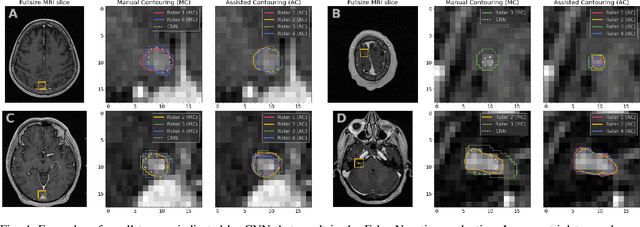

Abstract:We systematically evaluate a Deep Learning (DL) method in a 3D medical image segmentation task. Our segmentation method is integrated into the radiosurgery treatment process and directly impacts the clinical workflow. With our method, we address the relative drawbacks of manual segmentation: high inter-rater contouring variability and high time consumption of the contouring process. The main extension over the existing evaluations is the careful and detailed analysis that could be further generalized on other medical image segmentation tasks. Firstly, we analyze the changes in the inter-rater detection agreement. We show that the segmentation model reduces the ratio of detection disagreements from 0.162 to 0.085 (p < 0.05). Secondly, we show that the model improves the inter-rater contouring agreement from 0.845 to 0.871 surface Dice Score (p < 0.05). Thirdly, we show that the model accelerates the delineation process in between 1.6 and 2.0 times (p < 0.05). Finally, we design the setup of the clinical experiment to either exclude or estimate the evaluation biases, thus preserve the significance of the results. Besides the clinical evaluation, we also summarize the intuitions and practical ideas for building an efficient DL-based model for 3D medical image segmentation.